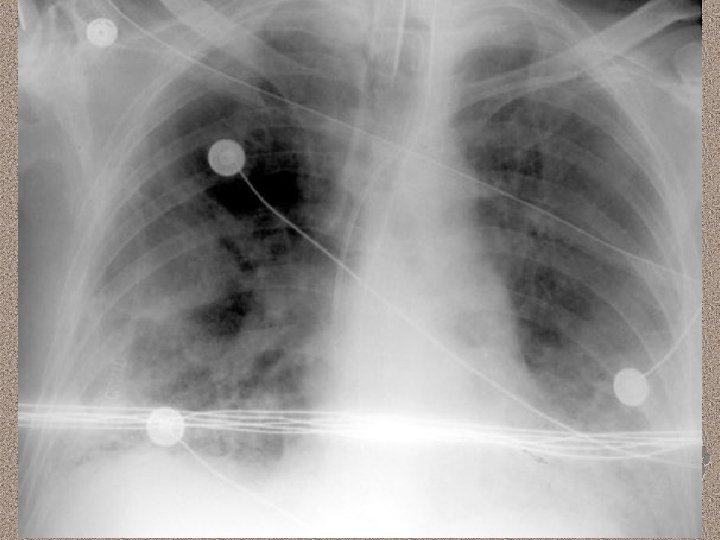

Definisi • Konferensi ARDS Amerika-Eropa 1994 • • • Gagal napas akut Pa. O 2 / Fi. O 2 < 200 mm. Hg Radiografi dada : infiltrat alveolar bilateral sesuai dengan gambaran edema paru • Tekanan baji kapiler pulmoner (pulmonary capillary wedge pressure) < 18 mm. Hg • Pa. O 2 / Fi. O 2 200 -300 mm. Hg Acute Lung Injury

Pemeriksaan Penunjang • Laboratorium • AGD : alkalosis respiratorik pada fase awal, dan berganti menjadi asidosis respiratorik pada fase lanjut • Leukositosis (sepsis), anemia, trombositopenia (SIRS), peningkatan kadar amilase (pankreatitis) • Gangguan fungsi ginjal dan hati. • Pencitraan • • Foto dada : gambaran radioopak difus CT-Scan : pola heterogen, predominasi infiltrat pada dorsal paru (supine)